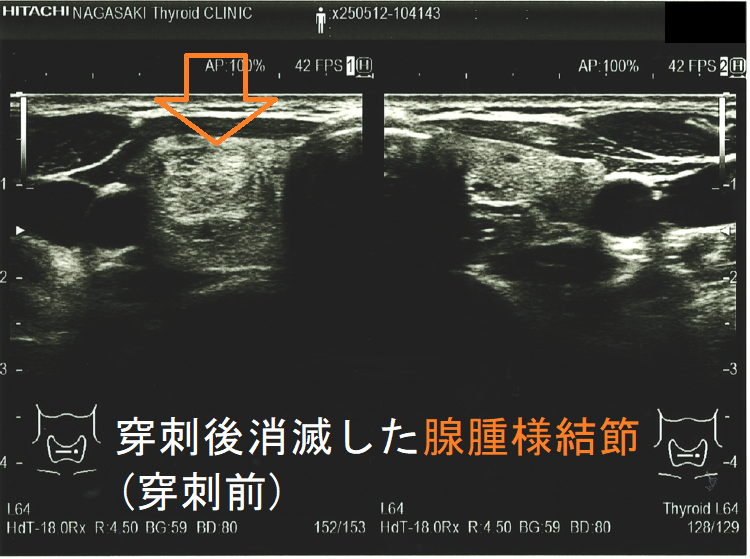

穿刺細胞診後内部融解

ケース①

ケース②